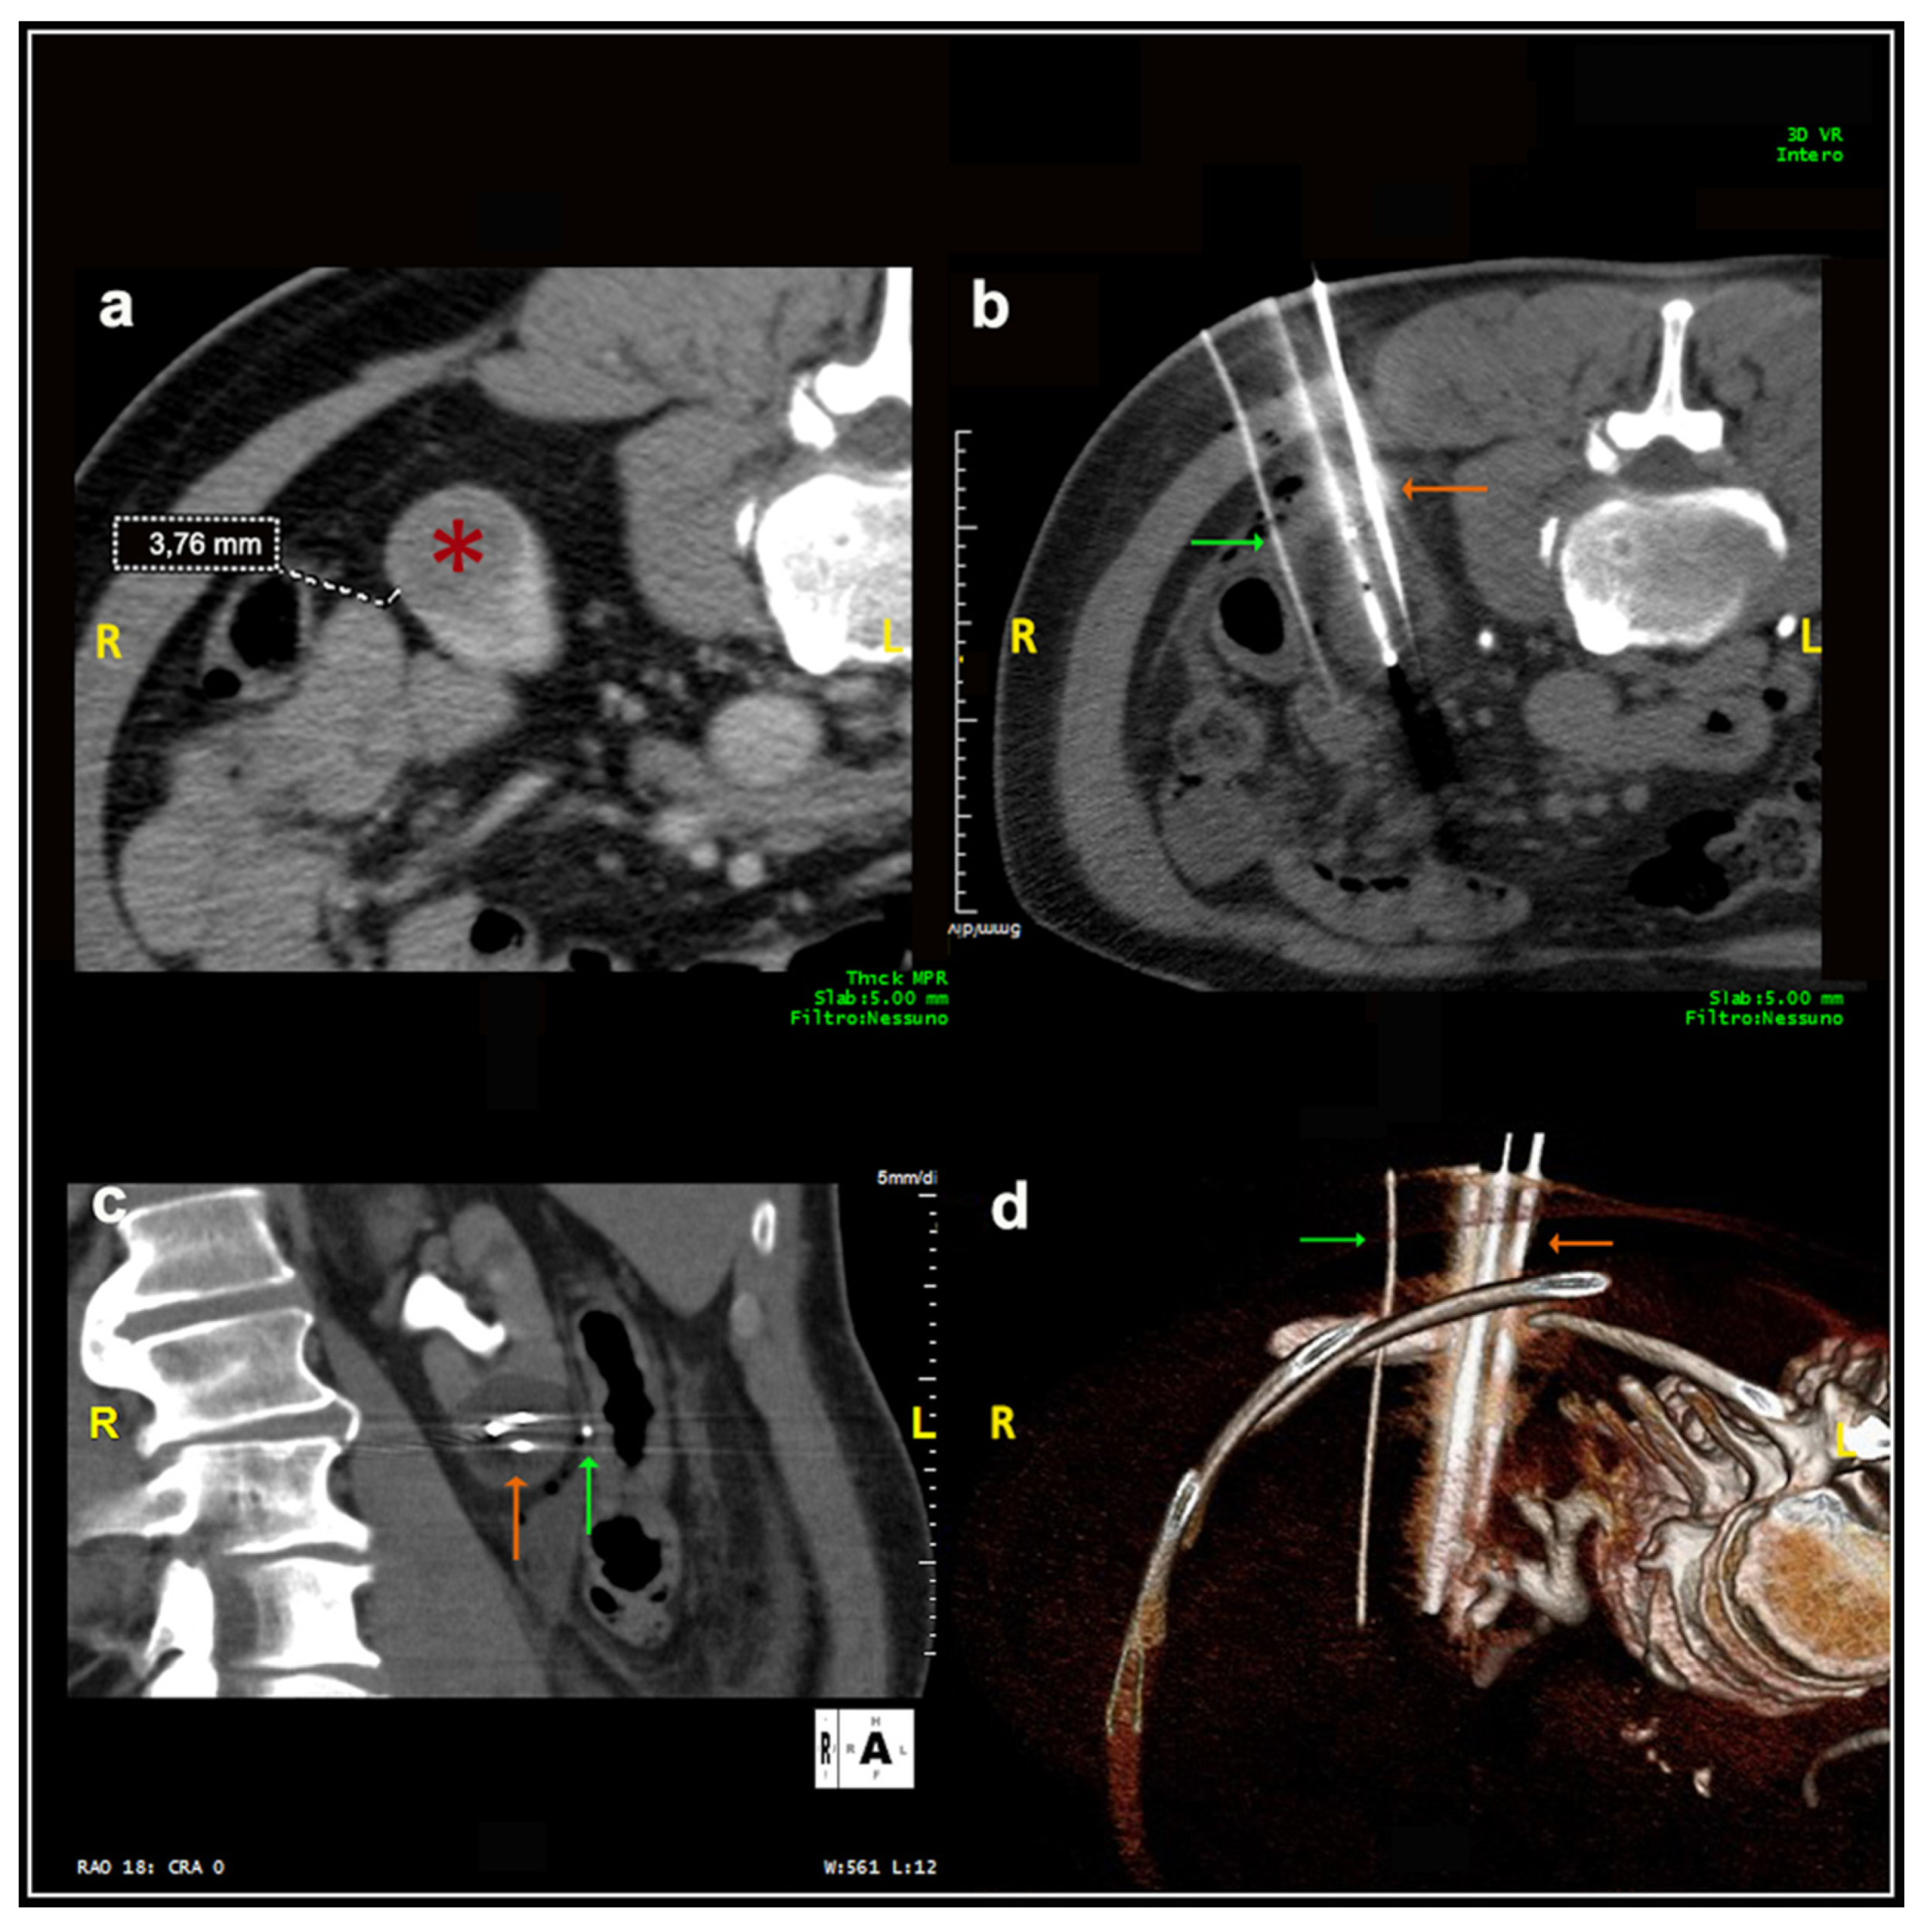

Most patients (87.4%) were treated prone. Twenty patients were treated in the oblique or lateral decubitus position (Figure 1). Only two treatments were carried out with the patient supine. Local anesthesia was mostly sufficient for the large majority of the procedures and mild conscious sedation was administered if needed. One patient required general anesthesia for the impossibility to collaborate with breath holds during the procedure because of dementia. In most cases, one lesion was treated in each procedure. In five patients, two lesions were treated in the same procedure, and, in another two patients, three lesions and four lesions were treated in a unique procedure, respectively. A median of two cryoprobes were used for each intervention (range: 1–8). Eight cryoprobes were required for the treatment of one of the largest tumors (5.4 cm), which revealed to be a clear-cell carcinoma at biopsy. The procedure was technically successful, and no complications occurred. Eighty-nine lesions required a complex cryoprobe approach. Hydro-dissection was necessary for the treatment of 13 tumors due to the vicinity of the bowel that could not be displaced after changing the position of the patient (Figure 2). In two cases, emptying of a cyst adjacent to the lesion was deemed necessary. Only one patient required a trans-hepatic approach (Figure 3). The procedures had a median duration time of 84 min (range: 40–153). Data on radiation exposure was available for 113 out of 138 patients with a median radiation exposure of 43.7 mSv.

Figure 2. Male, 75 years old. Hydrodissection technique. (a) At the initial scan, the distance between the lesion (*) and an intestinal loop was 3.76 mm, significantly inferior to the safety margin of 1 cm required. (b) A 16G needle cannula (green arrow) was inserted for the injection of sterile water to increase the distance between the structures. The lesion was adequately treated with three cryoprobes (orange arrow). (c,d): Coronal plane and 3D reconstruction images, respectively.